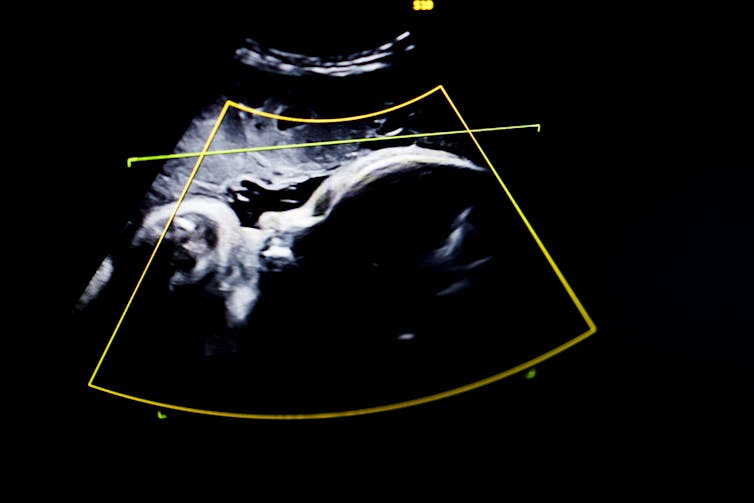

With current technology, preterm births are rarely preventable. Current screening tools to measure the risk of preterm birth are fairly primitive. Doctors use ultrasound to monitor the size and position of the baby, and they touch the cervix to feel whether it is softening, a normal process prior to labor but problematic if it is happening too soon.

One of us, Kristin Myers, studies the biology of tissue remodeling to quantify the biomechanics of pregnancy. Her lab creates computer models to measure how the uterus, cervix and fetal membranes work to carry the mechanical loads that pregnancy generates. She and her team use ultrasound to look at how the uterus grows and stretches and how much mechanical load is on the cervix, predicting whether it will fail too soon. Using the uterus as a pressure gauge for the mechanical environment of pregnancy could help identify problems before they occur.

Finally, Melissa Skala uses a noninvasive technique called optical coherence tomography. This imaging method produces 3D images of tissues that can’t be captured by ultrasound or MRI, such as extremely thin fetal membranes. Her lab used this technique to study how fetal membranes rupture under different pressures, providing a baseline of information that can be used to build better digital models of fetal membrane stress. Improved imaging of the fetal membranes and cervix can alert physicians to when these structures are at risk of failing.